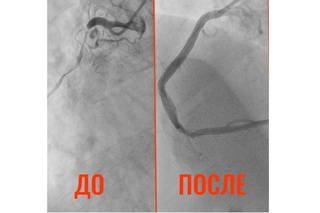

«Результаты суточного мониторирования по холтеру потребовали экстренной помощи. При выполнении коронарографии врачи были шокированы: сужение просвета коронарной артерии достигло 90%! Кровь почти перестала поступать к сердцу», — сказано в Telegram-канале медиков.

По словам специалистов, состояние сосудов 32-летнего мужчины сравнимо с изменениями, характерными для глубокой старости: были поражены все три коронарных артерии. Чтобы предотвратить инфаркт, врачи приняли решение об экстренной операции.

«3 марта пациенту провели стентирование. Установлено три стента, кровоток восстановлен полностью. Сейчас состояние пациента стабильно, впереди — реабилитация и консультации с областными коллегами по телемедицине», — поделились балаковские специалисты.